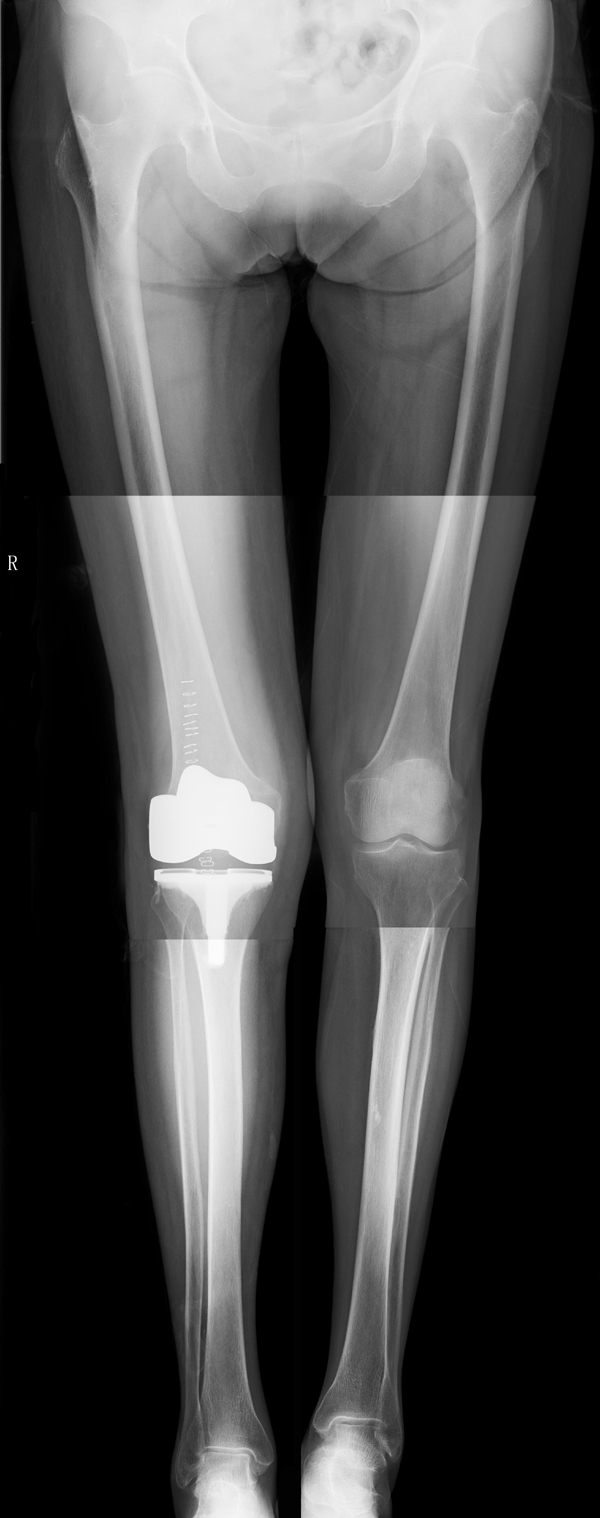

病例二:患者女性,82歲。主因“右膝疼痛10年伴加重、活動(dòng)受限半個(gè)月”入院。入院前右膝痛時(shí)好時(shí)壞,疼痛劇烈時(shí)無法站立。

患者術(shù)前全長

患者術(shù)后

患者術(shù)后全長